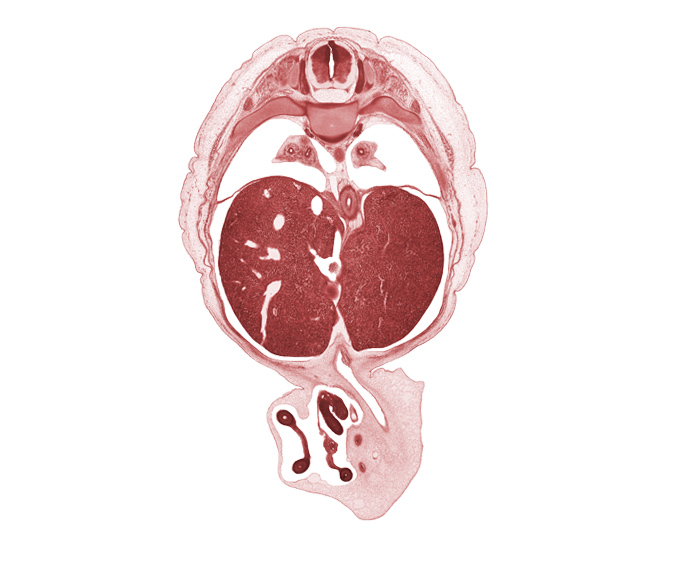

Carnegie Embryo #4090 | Location: 20-1

Keywords: T-8 spinal ganglion, afferent hepatic vein, aorta, distal limb of herniated midgut, esophagus lumen, iliocostalis muscle, left lobe of liver, longissimus muscle, lower lobe of left lung, lower lobe of right lung, proximal limb of herniated midgut, pylorus of stomach, rib 9, right lobe of liver, spinalis muscle, umbilical vein, umbilical vesicle stalk

Source: The Virtual Human Embryo.